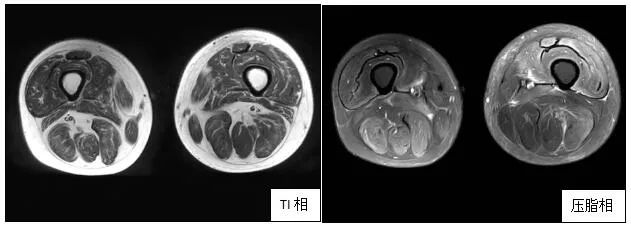

肌肉磁共振(2020年3月12日)显示患者双大腿肌肉明显萎缩;肌肉病理显示肌纤维坏死(黑箭头)、再生(红色箭头)

肌肉磁共振(2021年1月14日)显示患者双大腿肌肉较前明显恢复